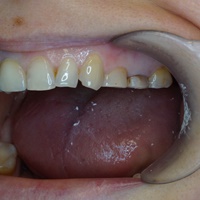

Wskazania do wykonania resekcji zębów 21, 22. Prawie niewidoczna blizna pooperacyjna.